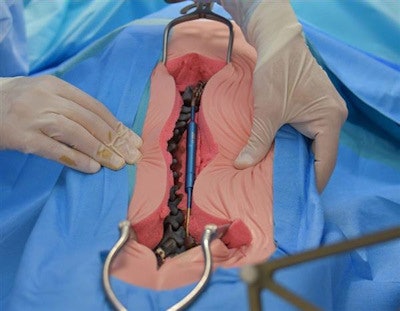

The team used their 3D-printed model of the child's spine to simulate a robot-guided minimally invasive procedure, which enabled them to perfect their timing and fine-tune their surgical precision. The challenge of inserting 7-mm iliosacral screws into a bone corridor that was 8-mm wide proved possible with the support of a robotic surgical assistant (ROSA, MedTech).